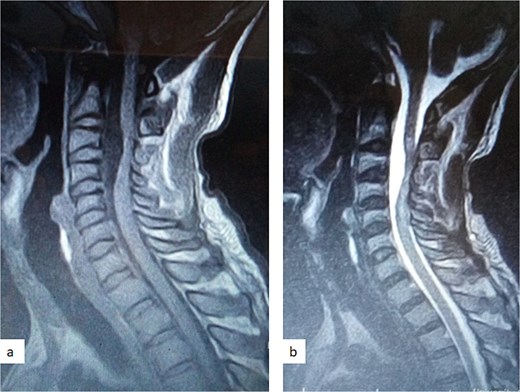

A 47-year-old man presented to us with progressive weakness of the extremities of 5 weeks duration. The weakness was first noticed in the left hand and progressed to involve the entire left upper limb and subsequently the right upper limb and the lower limbs. There was associated paraesthesia, constipation, and erectile dysfunction. Clinical examination revealed a middle-aged man with spastic quadriplegia and exaggerated muscle stretch reflexes. The sensory level was C4. Other systemic examination findings were normal. A clinical diagnosis of C4 non-traumatic myelopathy, Frankel B was made. Cervical spine MRI showed an intradural-extramedullary lesion with similar intensities to cerebrospinal fluid (CSF) on all sequences anterior to the spinal cord at C2–C4 with significant cord compression at C3–C4 and cord signal change on T2-weighted image at C2–C5 (Fig. 1). A diagnosis of cervical spine intradural AC was made. The lesion was accessed through C3–C4 laminectomies. At surgery, there was a cyst anterior to the cord with the latter flattened and displaced posteriorly. The cyst was excised completely and water tight dura closure done (Fig. 2). He made progressive post-operative neurological improvement and he was discharged on the 10th post-operative day. He was last seen 22 months post-surgery. At the time, he was ambulating without support, power was Grade 4+ to 5 in the upper and lower limbs.

Sagittal T1-weighted (a) and T2-weighted (b) cervical spine MRI images showing an intradural arachnoid cyst posteriorly displacing and compressing the spinal cord.

MRI is the imaging modality of choice for the diagnosis and follow-up of SACs [4]. It does not require intrathecal injection of contrast and demonstrates the location, size, extent, and nature of the cysts as well as neural elements compression and intrinsic cord changes among other features [7, 16–18]. On MRI SACs have similar signal intensities to those of CSF, hypointense on T1-weighted, and hyperintense on T2-weighted images [16]. Extradural cysts may show absent posterior epidural fat, epidural fat capping, and T2-hypointense cyst wall [16, 19, 20] (Figs 3 and 6b). Intradural cysts are characterized by widening of the subarachnoid space, displacement of the cord/cord compression and an undistinguishable cyst wall [2, 21] (Fig. 1). The site of communication between the cysts and subarachnoid may not be demonstrable on MRI [16]. Computed tomography myelograghy has been the imaging of choice in demonstrating the communicating site between the cyst and the subarachnoid cyst [16]. Newer MRI flow studies using cinematic MRI has proven to also be able to demonstrate the communication site [22].

(a) Sagittal T2-weighted cervical spine MRI image showing expanded subarachnoid space anterior to the spinal cord at C2–C4, posterior displacement and compression of the cord and cord signal change at C2–C5. The wall of the cyst is indistinguishable suggestive of intradural spinal arachnoid cyst. (b) Sagittal T2-weighted thoracic MRI image showing compression of the spinal cord anteriorly. There is visible hypointense cyst wall (arrow) suggestive of extradural cyst.